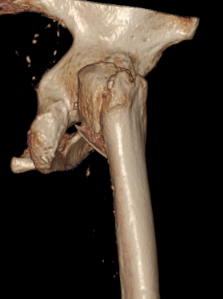

经详细检查,应奶奶被确诊为“右侧股骨粗隆间骨折”。这种骨折常被称为“人生最后一次骨折”,对于百岁超高龄老人而言,风险极高——长期卧床可能迅速引发肺部感染、深静脉血栓、褥疮等一系列致命并发症,保守治疗风险巨大。

骨科团队迅速评估病情,认为手术治疗是让老人重新站起来的唯一希望,也是降低长期卧床并发症风险的最佳选择。在科主任李忠教授带领下,唐炼副主任医师团队反复研究影像资料,精心设计创伤小、固定可靠的手术方案——微创闭合复位股骨近端防旋髓内钉(PFNA)内固定术。手术仅用时30分钟顺利完成。